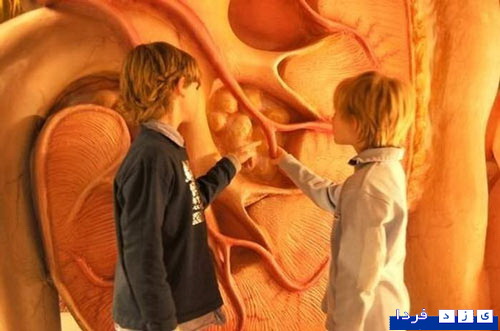

این ساختمان در هلند ساخته شده و با سفر به درون آن میتوان با بازدید از همه بخشها، از کارکرد درست یک بدن سالم آگاه شد و آموزش دید. ارتفاع این ساختمان که از نظر ظاهری پیکر انسانی نشسته است، 35 متر است.

این تصاویر عجیب و بی نظیری كه مشاهده می کنید مربوط به یك ساختمان واقع در كشور هلند است كه شبیه انسان ساخته شده و از تاریخ چهاردهم مارس 2008 برای بازدیدكنندگان فعال بوده است. بطوریکه با سفر به درون آن میتوان از تمامی قسمت ها و کارکرد درست یک بدن انسان سالم اطلاعات لازم را کسب کرد و در این تجربه جدید برای بازدیدكنندگان خصوصا دانشجویان رشته پزشکی این امکان فراهم شده بود تا با قسمتهای داخلی بدن انسان و نحوه فعالیتهای آنها از نزدیك آشنا شوند.

این بنای انسانی که از نظر ظاهری پیکر انسانی نشسته است، در كنار یك ساختمان شیشه ای با ارتفاع 35 متر بنا شده كه در جوار اتوبان A44 آمستردام به هاگو (Hague) قابل مشاهده است. گرچه این تصاویر شاید برای شما دوستان پرشین استار چندان جدید نباشد ولی آنچه مهم است اهمیت آموزش و ایجاد انگیزه برای سهولت در شناخت و درک بهتر ساختمان پیچیده و اسرار آمیز بدن انسان نسبت به نیاز محققین و دانش اندوزانی است که مایلند به گوشه ای از اسرار عظمت خلقت خداوند که همان اشرف مخلوقات است دست یابند.